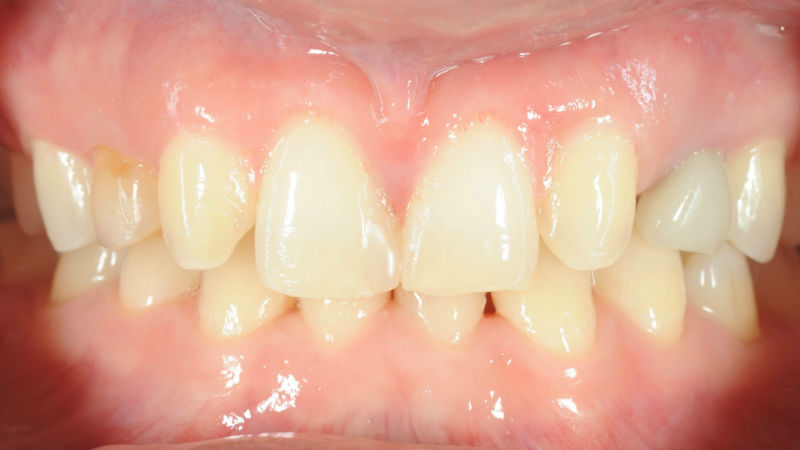

– Състояние на зъбите преди започване на лечение с алайнери